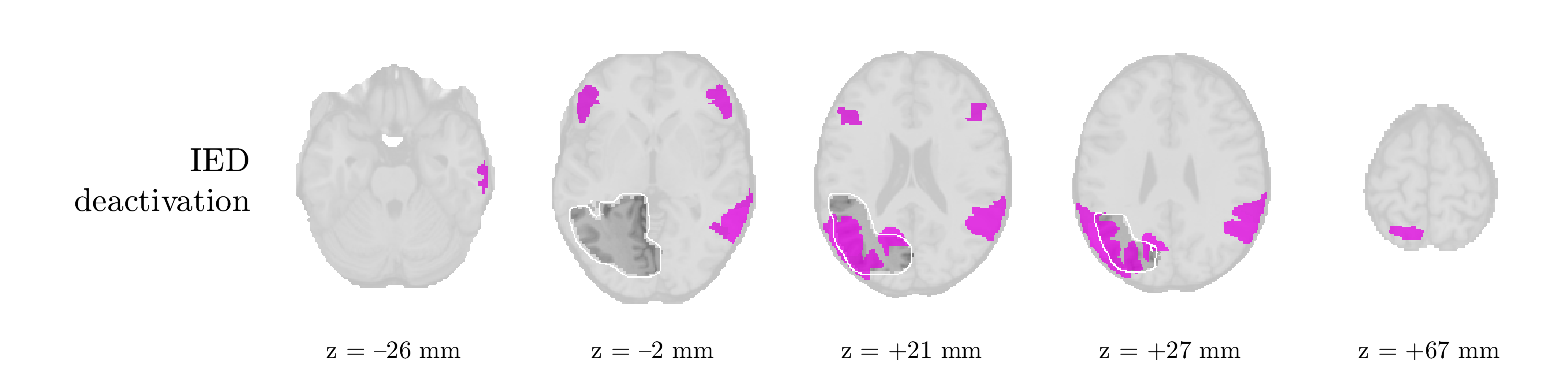

We analyze the solution with sources. Figure 1 shows the EEG signatures and HRF waveforms. One of the sources is highly correlated to the MWF reference (in grey), which was already known from Table B.3. This IED-related source had a typical low-frequency spectrum, which is expected for the typical spike-and-wave interictal discharges. The topography is relatively diffuse, although the highest amplitudes are mostly in the left hemisphere. This is in accordance with the lateralization of ictal onset zone (left temporal lobe, cfr. Table 1). There are some noteworthy observations to be made about some of the other components. The fourth has an unusually sharp spectrum, is mainly localized on two nonadjacent center electrodes, and is sustained for a single period of many seconds Hence, this component likely captured an artifact (of yet unknown origin), although we spotted no large-amplitude changes in the EEG itself. Similarly, the third source is only present at one frontal electrode, and exists in a frequency range above 20 Hz. It might represent a muscle artifact, e.g., due to frowning or twitching of some muscles in the forehead. The HRFs of all ROIs are shown in Figure 1(b). Two of the basis functions seem to have converged to a very similar waveform, which is an unfortunate possibility if two initial HRFs are too close to the same local optimum in their respective parameters. This reduces the expressive power of the basis set, which is clearly visible, since many ROIs have a nearly identical HRF. One of the twenty ROIs with the highest-entropy HRF overlapped the IOZ, although clearly this HRF (bold line) is not among the most dissimilar waveforms for this patient. This is also visible in Figure 2: both the HRF entropy and extremity maps show a small overlap with the delineated IOZ. Despite the good correspondence in the EEG domain, no significant (de)activation of the IED-component is found inside the IOZ.

We analyze the solution with sources, and show the results in Figure 3 and 4. As for patient 1, we found a source which is strongly correlated to the MWF envelope, and which had a mostly low-frequency behavior characteristic for spikes. The topography is mostly uninformative, and does not clearly correspond to the patient’s clinical data. The third source is mostly present at both sides of the head, is very sparsely active in time, and has a high-frequency content: this is most likely an artifact due to the neck muscles. Again, there is one of the highest-entropy HRFs which belongs to a ROI in the IOZ. Now, the waveform is clearly resolved from the other HRFs, through the strong initial dip (before 0 seconds). Such a dip is sometimes observed in HRFs, but its underlying physiological mechanism is not yet fully understood. It is possible that this dip reflects altered vascular autoregulation near the IOZ (cfr. the explanation in the Section 1 of the main text), or a rapid depletion in oxygen due to IED generation (before the IED becomes visible on the EEG). Figure 4 furthermore shows that the IED-related component is significantly active in parts of the IOZ, and deactive in others. As mentioned earlier, this deactivation may or may not be due to errors in sign correction. Interestingly, the ROI with the high alteration in neurovascular coupling is distinct from both the activated and deactivated ROIs.

We analyzed the solution with sources, and show the results in Figure 5 and 6. There is one source which is mostly correlated to the reference (but not extremely, see also Table B.3). This source had a right-temporal focus, conform the diagnosis in Table 1. The second source illustrates the phenomenon of an erroneous sign exchange between the spatial and spectral profiles. Also one of the HRFs has a negative polarity, which is a failure of the sign correction procedure (in this case, because there is exceptionally no positive overshoot). However, the HRF variability metrics are still interpretable, and indeed two ROIs among the ones with the highest-entropy HRFs overlap with the IOZ. The IED component is significantly active in a tiny portion of the IOZ (cfr. Figure 6). The second source is significantly active in symmetrical parts of the parietal lobe. Given its ongoing fluctuation over time, we hypothesize that this source captures a resting state network (RSN).

We analyze the solution with sources, and show the results in Figure 7 and 8. There is a clear IED-related component, with a very high correlation to the MWF reference, a typical spectrum, and an anterior-temporal focus, which corresponds very well to the patient’s diagnosis (cfr. Table 1). The fifth source seems present at only one channel, and has spectral harmonic at Hz and Hz. One of these peaks is reminiscent of the fourth component in patient 1. As Figure 8 shows, the HRF entropy and extremity prove to be strong biomarkers for the IOZ in this case, and also the significant IED activation and deactivation allow correct localization. In Figure 7, it is clear that some HRFs may still have the wrong sign, which means that the interpretation of ‘active’ and ‘deactivated’ is flipped in those ROIs. Hence, regions of significant deactivation are in fact significantly activated. The fourth source had a significant overlap with the auditory RSN, and its spectrum reveals activity in the band.

We analyze the solution with sources, and show the results in Figure 9 and 10. One source is strongly correlated to the MWF, while the other source is likely an artifact, given its very sparse temporal profile. Both sources coincide at one high-amplitude peak, by which we infer that this is probably an artifactual period in the signal. Indeed, when inspecting the original EEG signals, we found high-frequency muscle artifacts at these times. This source also had no significant activation in its spatial map, which corroborates its non-neuronal origin. The IED-related source had a broader spectrum than most other cases, and an uninformative topography. None of the ROIs with high-entropy HRFs is located in the IOZ. The pseudo t-map provides correct localization of the IOZ, however.

We analyze the solution with sources, and show the results in Figure 11 and 12. We found a clear IED-related component, with a characteristic spectrum and a topography which is backed up by the patient’s diagnosis (left anterior-temporal IOZ). The fourth source has a very similar topography and spectrum to the fifth source in patient 5. One HRF inside the IOZ had a high-entropy, and is distinguishable from the others by its very sluggish waveform, i.e., it is smeared out in time, with no sharp over- or undershoot. Also the pseudo t-map provided an accurate localization of the IOZ. Notably, in this patient, the extremity metric misses the deviating HRF in the IOZ (while the entropy metric picks it up). The second source overlapped with the frontal part of the default mode network (DMN), and is active in the and low bands.

We analyze the solution with sources, and show the results in Figure 13 and 14. We found two components which had correlated time courses. At the time of the peaks, we found higher-amplitude events in the EEG with dubious origin, hence they may or may not be artifacts. One of both components is more strongly correlated to the MWF, and its activation is concordant with the IOZ. The second component shows high overlap with the sensorimotor network. For this patient, none of the IOZ’s ROIs had extreme values of either HRF metric.

We analyze the solution with sources, and show the results in Figure 15 and 16. In this patient, there is only a moderate correlation of a component with the MWF reference time course. This component’s topography (left occipital) agrees with the clinical description, however. The HRF extremity (and not the entropy) is high in a small part of the IOZ. Both the significant IED activation and deactivation allow correct localization as well. The second source seemingly captured high-frequency oscillatory activity in the sensorimotor network, similar to the previous patient.

We analyze the solution with sources, and show the results in Figure 17 and 18. The IED-related source had a high correlation with the MWF reference, but an odd bimodal spectrum. Its EEG topography is very consistent with the clinical description. Both HRF extremity and entropy are useful biomarkers for the IOZ. The IED activation and deactivation maps each had a very small overlap with the IOZ. The second source is temporally sparse and captures high-frequency EEG variations, which we identified as muscle artifacts.

We analyze the solution with sources, and show the results in Figure 19 and 20. Again we observe an IED-related source and a seemingly artifactual source with a spectral peak near 34 Hz. Many of the high-entropy HRFs are highly noncausal, and are associated to ROIs inside the IOZ. Hence, with both HRF metrics, the highest-scoring ROIs provides good localization of the HRF. While there are no significantly active ROIs in the IOZ, there are several significantly deactivated ROIs, which may indicate that the sign standardization was not done flawlessly (cfr. also some of the negative-peaking HRFs for patient 10). Surprisingly, the second source had one significantly active ROI, which overlaps with the IOZ, but which did not match its EEG topography. Hence, the nature of this source remains ambiguous.